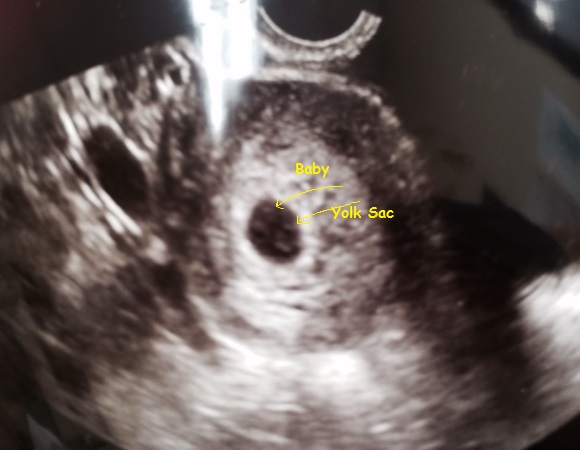

Transvaginal & Sagital view, as far as I could tell.

Very quick internal scan, they think I am 5wks+6-6wks... Gender guessing & stressing makes me wish I could have a :beer:!

Attachment 23406